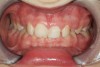

Figure 8   Young adult with signs and symptoms of the bruxism triad: Lateral tooth wear, erosive and abrasive damage to the teeth, and a history of moderate apnea.

Figure 8

Figure 9   Extensive erosive wear. Airway improvement can reduce GERD and GERD resolution can reduce sleep bruxism.

Figure 9

The bruxism triad coupled with nocturnal hyposalivation or xerostomia appreciably increases the risk of frictional and erosive tooth wear.12,18 The bruxism triad is composed of arousal-induced tooth grinding, airway-associated sleep disorders, and sleep-related GERD (Figure 8 and Figure 9). While a causal relationship has not been established, significant correlation makes it important for dentists to evaluate their patient population.